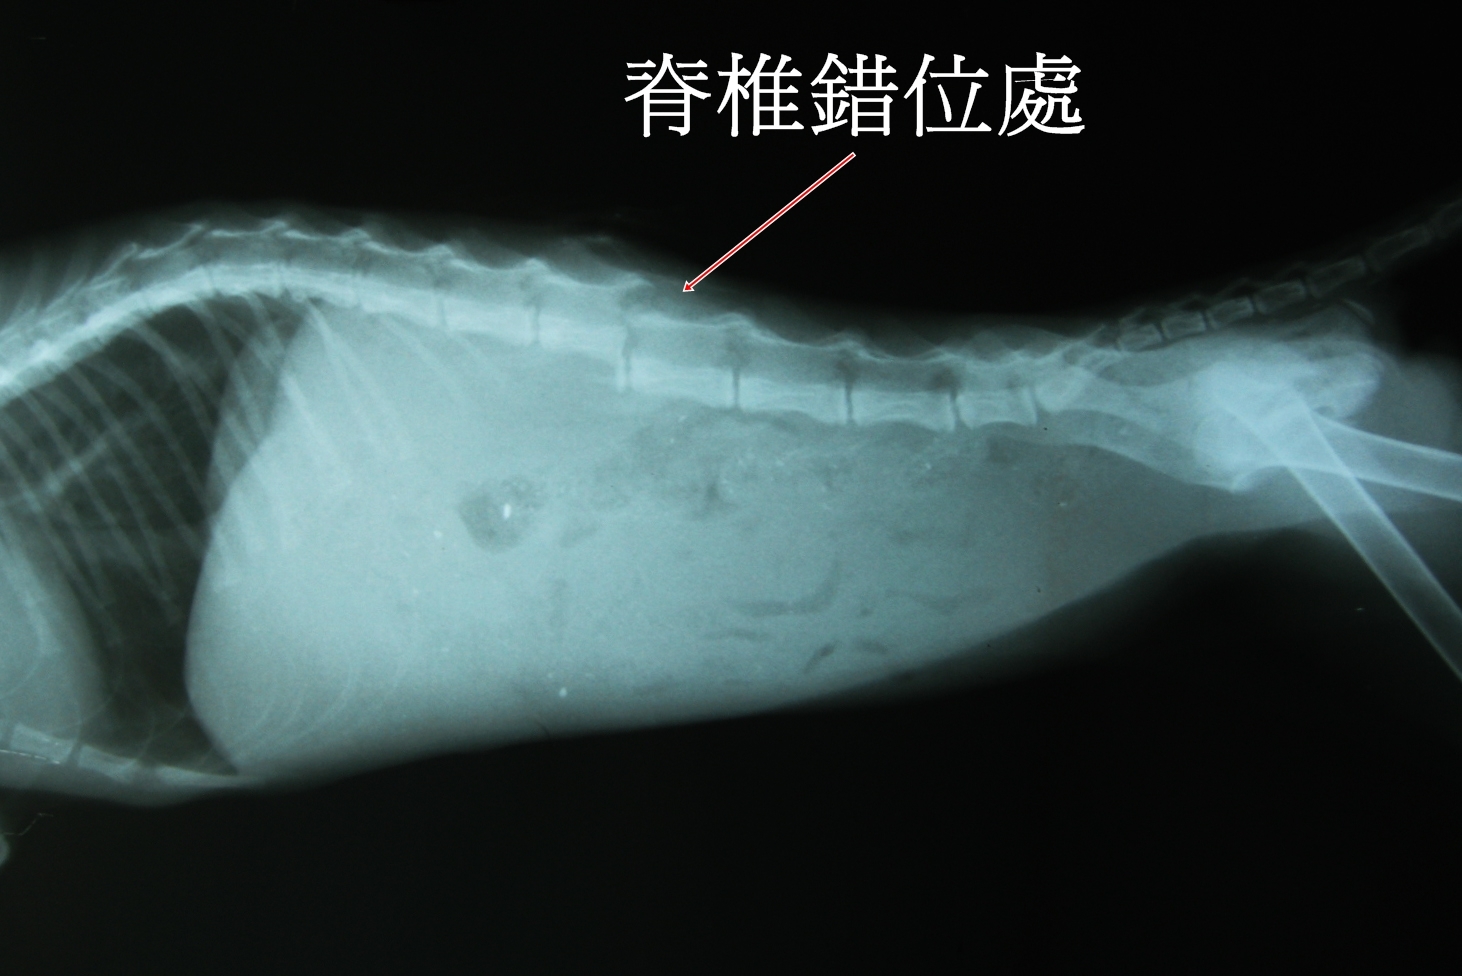

已完成醫助款案例 |